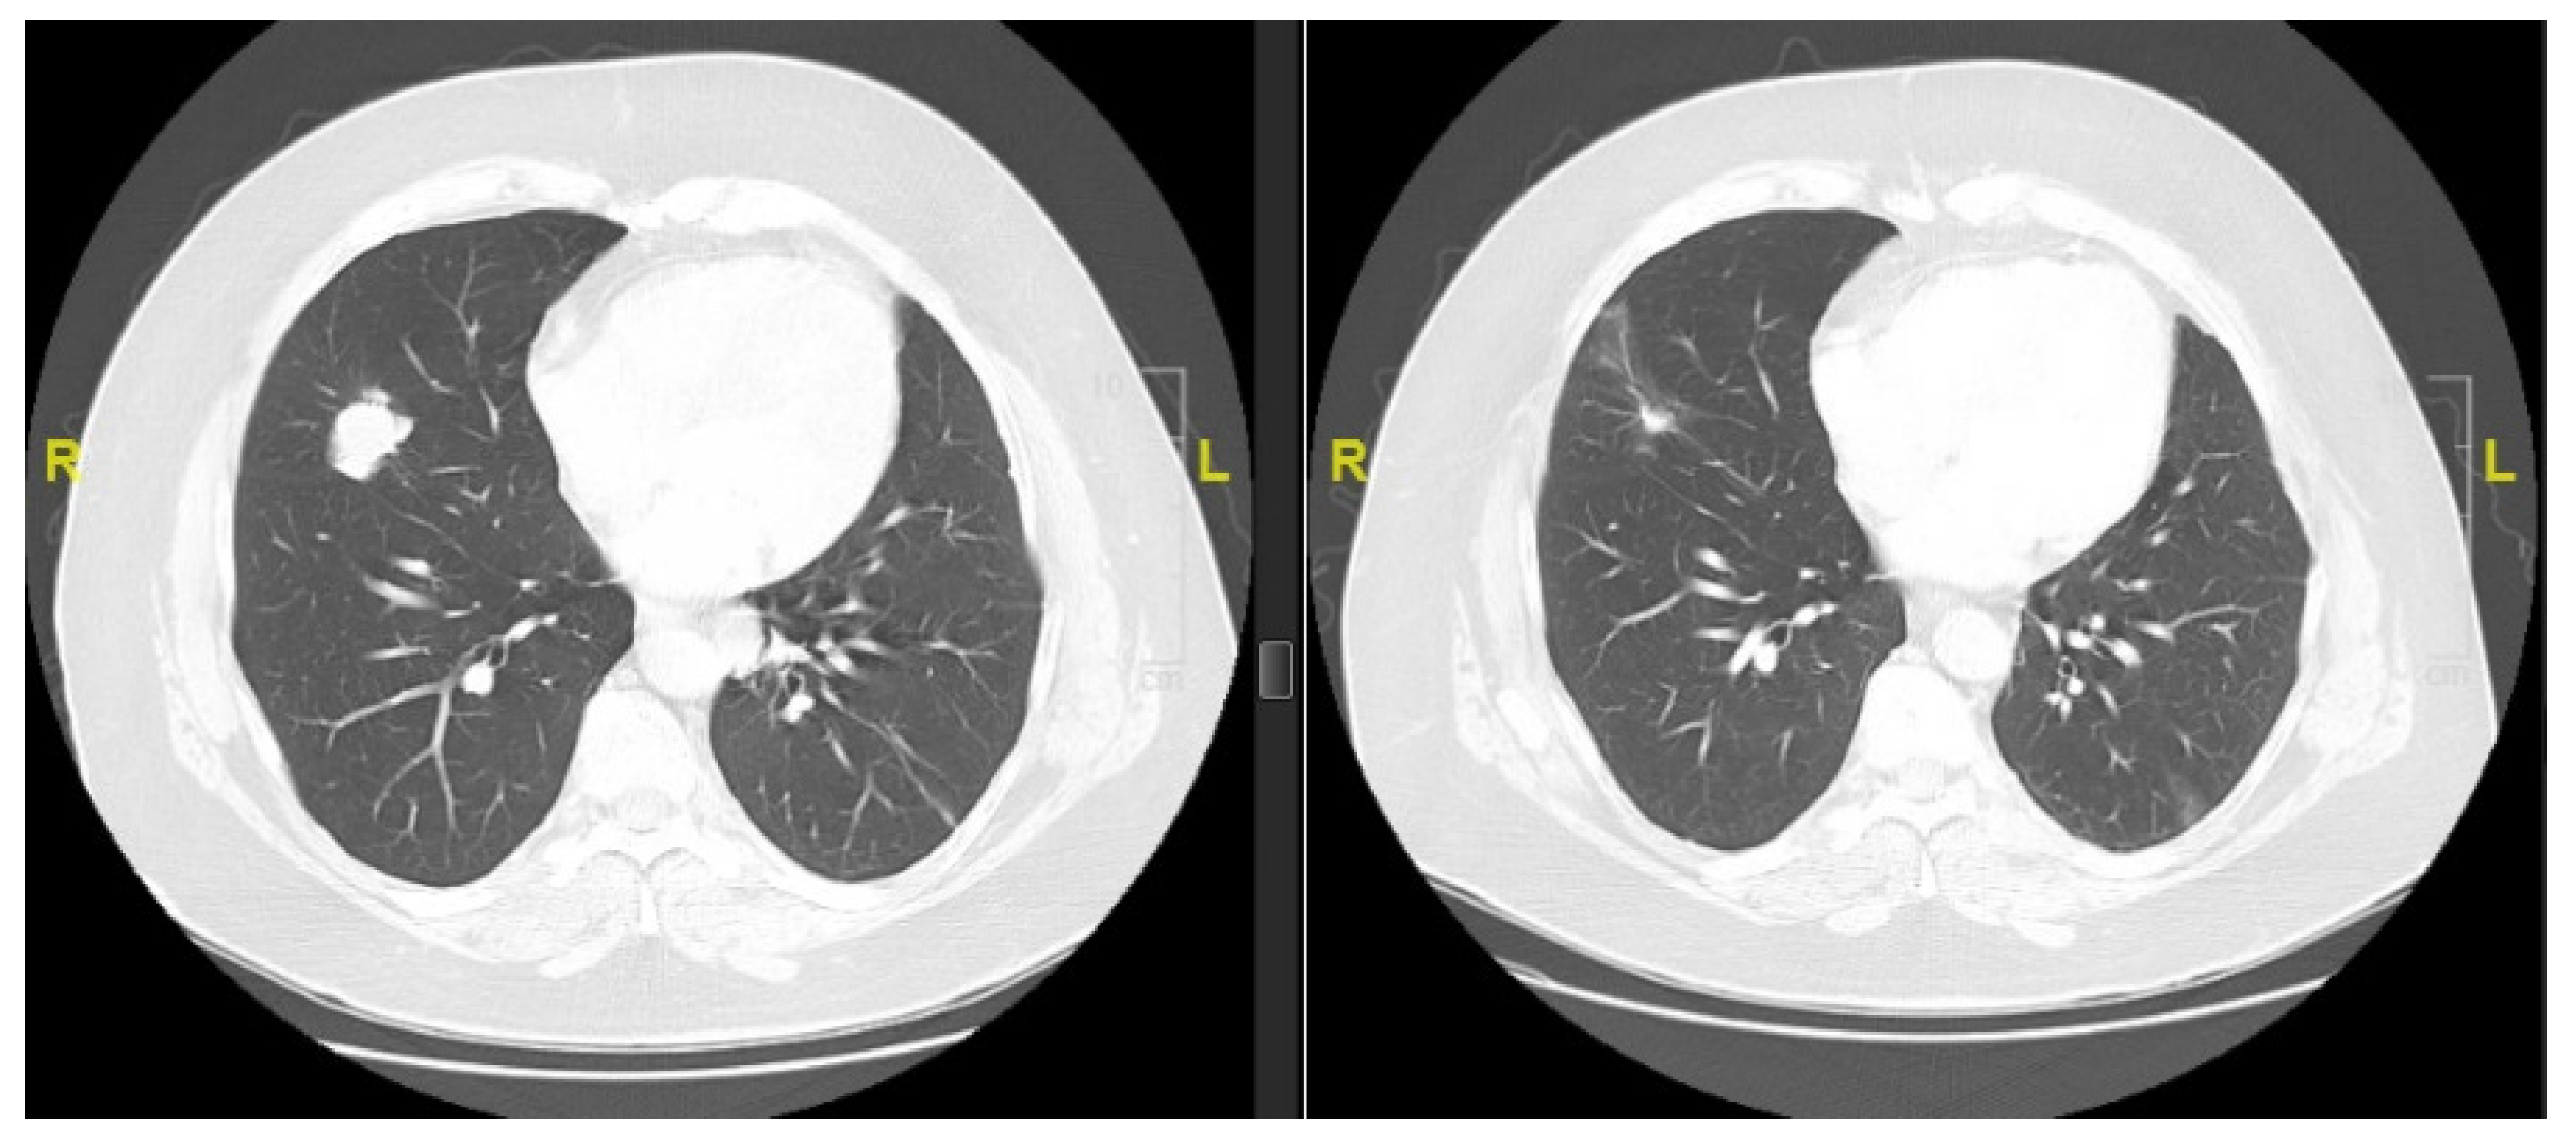

| Lung | 38 (90%) |